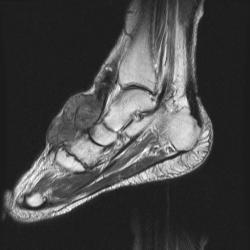

сагиттальная Т2

На серии МР-томограмм получены изображения правого голеностопного сустава.

На тыльной поверхности правой стопы, непосредственно под кожей в области таранной, ладьевидной, клиновидных и оснований от первой до третьей плюсневых костей определяется патологическое образование (тофусы), с распространением на медиальную поверхность стопы, образование неоднородной структуры и МР-сигнала, умеренно гиперинтенсивное на Т1 ВИ, гипоинтенсивное на Т2 ВИ и неоднородного на FAT SAT ИП. Размеры образования 35 х 65 х 40 мм. На постконтрастных изображениях отмечается значительное диффузное усилением интенсивности МР-сигнала от образования. Аналогичные по МР-характеристикам образования, меньших размеров выявляются в левой стопе.

Со стороны костной системы определяются: единичные костно-хрящевые дефекты со склерозом по периферии, диаметром до 3 мм, располагающиеся в субхондральных отделах в области суставных концов большеберцовой и малоберцовой костей, в области прикрепления длинной подошвенной связки к подошвенной поверхности пяточной кости. Множественные дефекты диаметром до 9 мм расположены в области смежных поверхностей ладьевидной и клиновидных костей, некоторые кистовидные дефекты вскрылись в мягкие ткани.

В пяточной кости правой стопы, определяется округлая зона повышенной интенсиновсти МР-сигнала на всех импульсных последовательностях в области блока малоберцовой кости, размерами 7 х 8 мм.

Суставные поверхности уплощены, суставные щели резко сужены, местами определяются краевые костные разрастания.